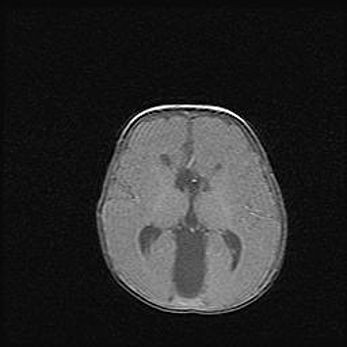

Лейкомаляция с кистозно-глиозной дегенерацией головного мозга.

Возраст: 2 месяца 25 дней

Вес: 6400 г

Окружность головы: 40 см

Срок гестации: 41 неделя

Лейкомаляцию относят к ишемически-гипоксическим повреждениям головного мозга, диагностируемым у новорожденных. При лейкомаляции в головном мозге обнаруживают очаги некроза, возникшие после тяжелой гипоксии и нарушения кровотока. В процессе морфогенеза очаги проходят три стадии: 1) развития некроза, 2) резорбции и 3) формирования глиозного рубца или кисты. Перивентрикулярная лейкомаляция (ПЛ) встречается примерно в 12% случаев среди новорожденных, обычно – у недоношенных детей, причем, частота ее зависит от массы, с которой младенец появился на свет. Наибольшее число малышей страдает лейкомаляцией, если масса при рождении 1500-2500 г.